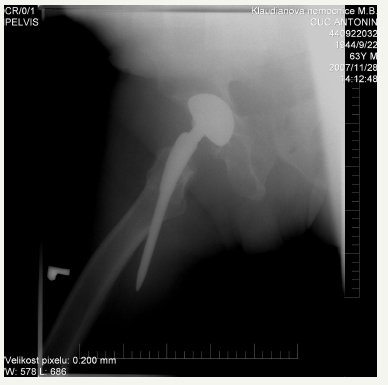

When MUDr. František Vurm illegal finished the assembling the set THA-Bi contact S, Non-cemented, Dimension 13 mm, Type N from the B. Braun Germany…out of mandatory accuracy in coaxial ties the femoral bone and there Stem….out of tolerance +/- 1 grads… when he placed the stem illegally crummy ….with declination in the sagittal Direction (the same Plaine and declination of the axes of the Stem on 13,68 grads- Direction as the Imaging RTG since the November 16, 2007). Only Idiots or Murders could say „It is no to detect-illegal declination on the RTG since the date November 16, 2007“. We should observe the post operational Image not illegally „in the hand and with intuitive views “! We should take always the Firm installing radiological masks and on the Orthopaedic screen, we should comparing the placement on the Image with this radiologic firm etalons….and when the spice of the used stem in the coordinates Xi, Yi, Zi we were controlling….by the Preliminary Planning…. but there are in the FALSE DEPTH! The spice it is about 5,8 millimetres in femoral axes „virtually shorten axes of the Stem “-Only idiots or my Murders, could say again by Court dealing….it was LEGE ARTIS CZ!

No, there are by the goniometric Algorithm to evidence the same declination 13.68 Grads definitely, as we could see the same declination on the next post operational RTG Image since the date November 28, 2007 before Reoperation THA! It was Crash FAUSSE ROUTE STEM of the false illegal assembling product „CE“, there were no functional mandatory abilities by official testing of implanted product „CE“ on the surgery hall since date November 13, 2007!

Figure 1:

Figure 2:

There are absolutely excluded to substitute the real Phenomenon’s and Biomechanics, Geometry, Radiologic evidences from Tragic Crash FAUSSE ROUTE in the surgeon Hall since date November 13, 2007-see the next 2 post operational RTG Images“ and the False Medical Hypotheses from the Court Medical Message from the date March 27, 2012 from the Knowing Medical Institute- The Central Army Hospital Prague CZ Post operational patient Fallen with perfect Lege Artis CZ the Provider Health Care-the Regional Hospital Mladá Boleslaw with medical staff-Orthopaedist MU Dr. František Vurm, prime MUDr. Pavel Šedivý. The False Medical Court Message was signed by the Head of The Central Army Hospital Prague CZ-Prof. MU Dr. Miroslav Zavoral Dr Sc., so as the Head of the Army Forensic Clinic prime MUDr. Miloš Sokol Ph. D., No. 36 C 181/2009-123 since March 27, 2012 (Figure 1 & 2).